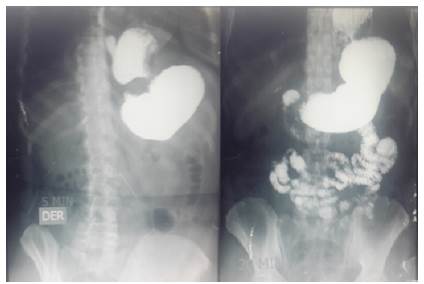

Una radiografía de serie digestiva alta reportó hernia hiatal paraesofágica con disminución del calibre en la parte alta de la cavidad gástrica y paso normal del contraste al intestino delgado y colon (figura 2).

Fuente: archivo clínico.

Figura 2 Serie digestiva alta preoperatoria. Obsérvese la imagen en reloj de arena y el paso del contraste hacia el intestino delgado